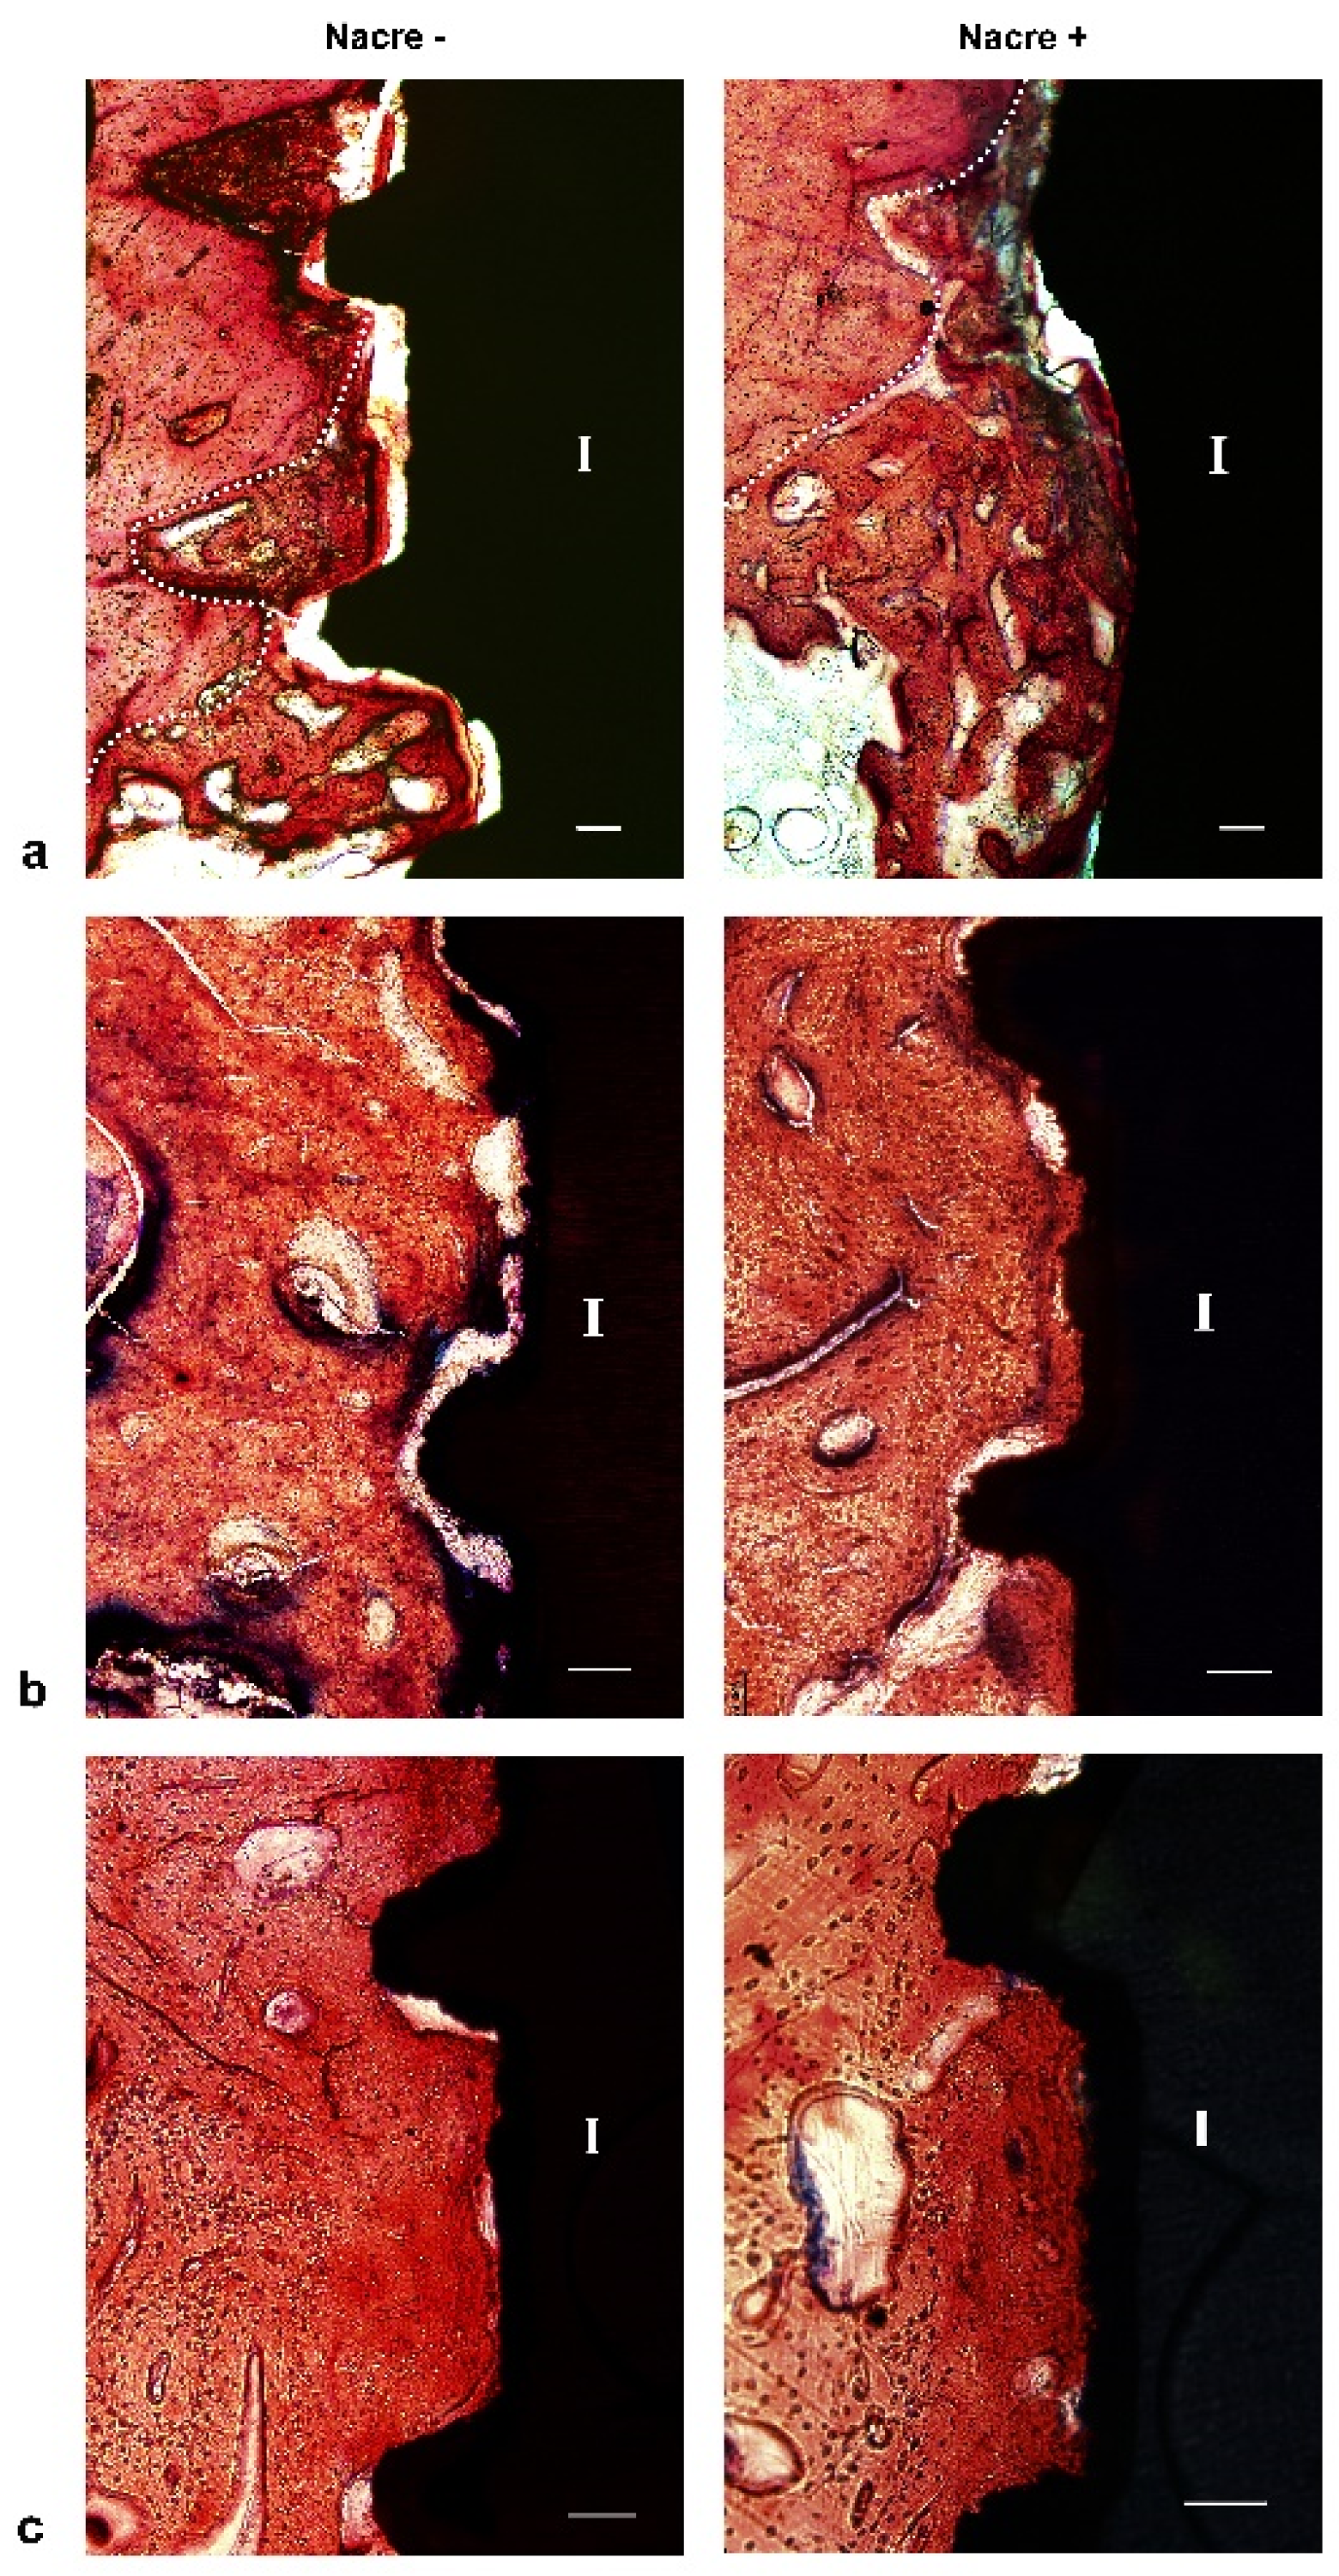

2.3. Histological Study